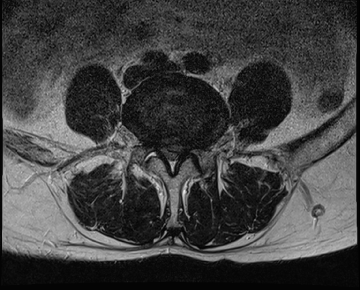

요추 협착증 수술 전·후

2020.08.30

2022.09.06

ㆍ환자 동의를 받은 자료이며, 이미지 사진은 실물과 다를 수 있습니다.

ㆍ모든 자료는 새움병원 자료입니다.